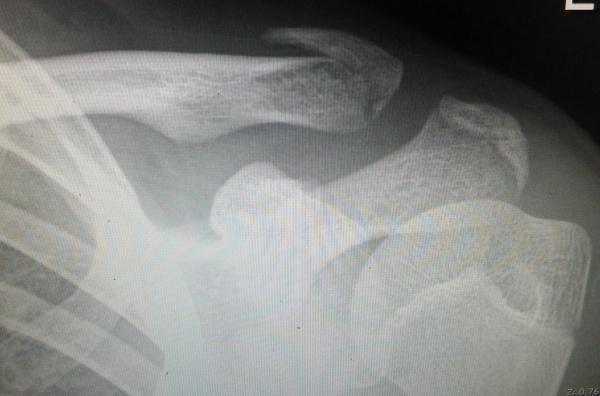

儿童锁骨青枝骨折图片

儿童锁骨青枝骨折图片,儿童青枝骨折图片

儿童锁骨外侧端骨折

儿童锁骨骨折图片

儿童锁骨骨折

儿童锁骨x光